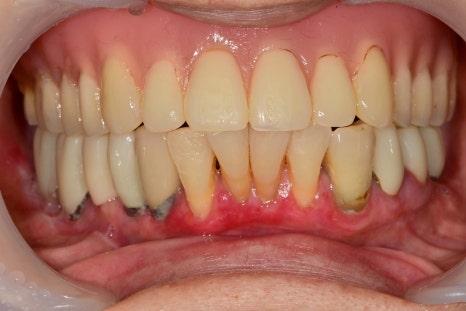

아래 잇몸이 아파요

처음 내원은 아래치아 주변 잇몸이 아프셔서 내원해주셨습니다.

일단 임플란트, 앞니 주변이 잇몸이 부어있었기 때문에

먼저 잇몸치료를 진행하고 그 이후에 임플란트 진단을 했습니다.